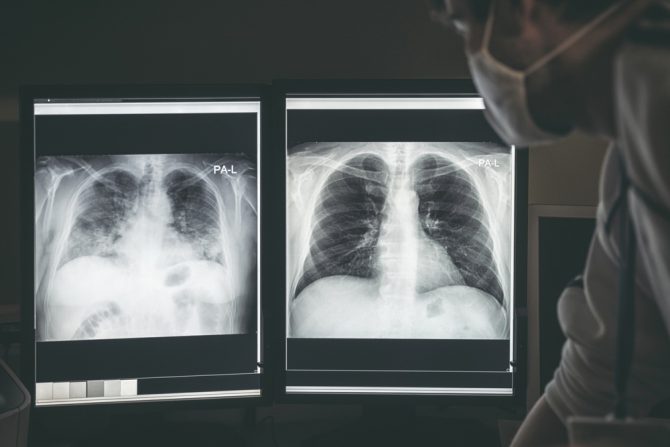

Dr Ghassan Kamel, načelnik odeljenja SSM Health SLU bolnice u Sent Luisu, uporedio je dva rendgenska snimka njegovih pacijenata pozitivnih na covid 19, jednog vakcinisanog i jednog koji nije imunizovan. Fotografije koje je napravio pokazale su jasnu razliku u stanju pluća zaraženih, pa je to još jedan dokaz o važnosti i potrebi vakcinacije što većeg broja ljudi.

Šta znači bela boja na snimku pluća nevakcinisanog, a šta crna kod vakcinisanog

Kod nevakcinisanog pacijenta, slika je vidno zamagljena belom bojom, a dr Kamel objašnjava da bi to mogle da budu bakterije, sluz ili izlučevine.

- U slučaju ovih pacijenata najverovatnije bi bila potrebna barem kiseonička potpora, a za neke se ne može isključiti ni intubacija, sa ostalim terapijskim protokolima, uz uključivanje sedativa, ako dođe do potrebe za respiratorom i održavanjem života - objašnjava dr Kamel.

Kod vakcinisanog pacijenta slika je, međutim, mnogo jasnija. Kako podseća dr Kamel, ova pluća na rendgenskom snimku izgledaju tamno, sa više boje, a to je slučaj kada su normalno ispunjena vazduhom. Prema njegovim rečima, vakcinisanim osobama, koje se ipak zaraze korona virusom, uglavnom nije potrebna intenzivna nega, za razliku od nevakcinisanih, osim ako nemaju već postojeće komorbiditete ili su ozbiljnije imunokompromitovani.